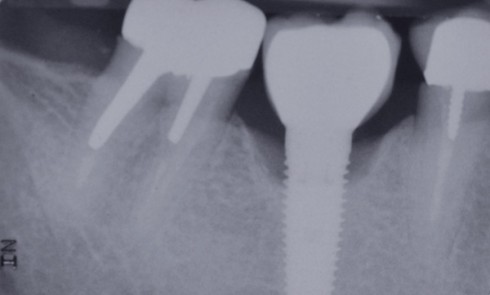

Dès 1997, Cordioli et al. [2], s’interrogeant sur le nombre d’implants nécessaires pour assurer la rétention d’une prothèse complète amovible...

Une patiente consulte car elle ne supporte plus le port de sa prothèse amovible mandibulaire, pourtant suffisamment stable grâce à...